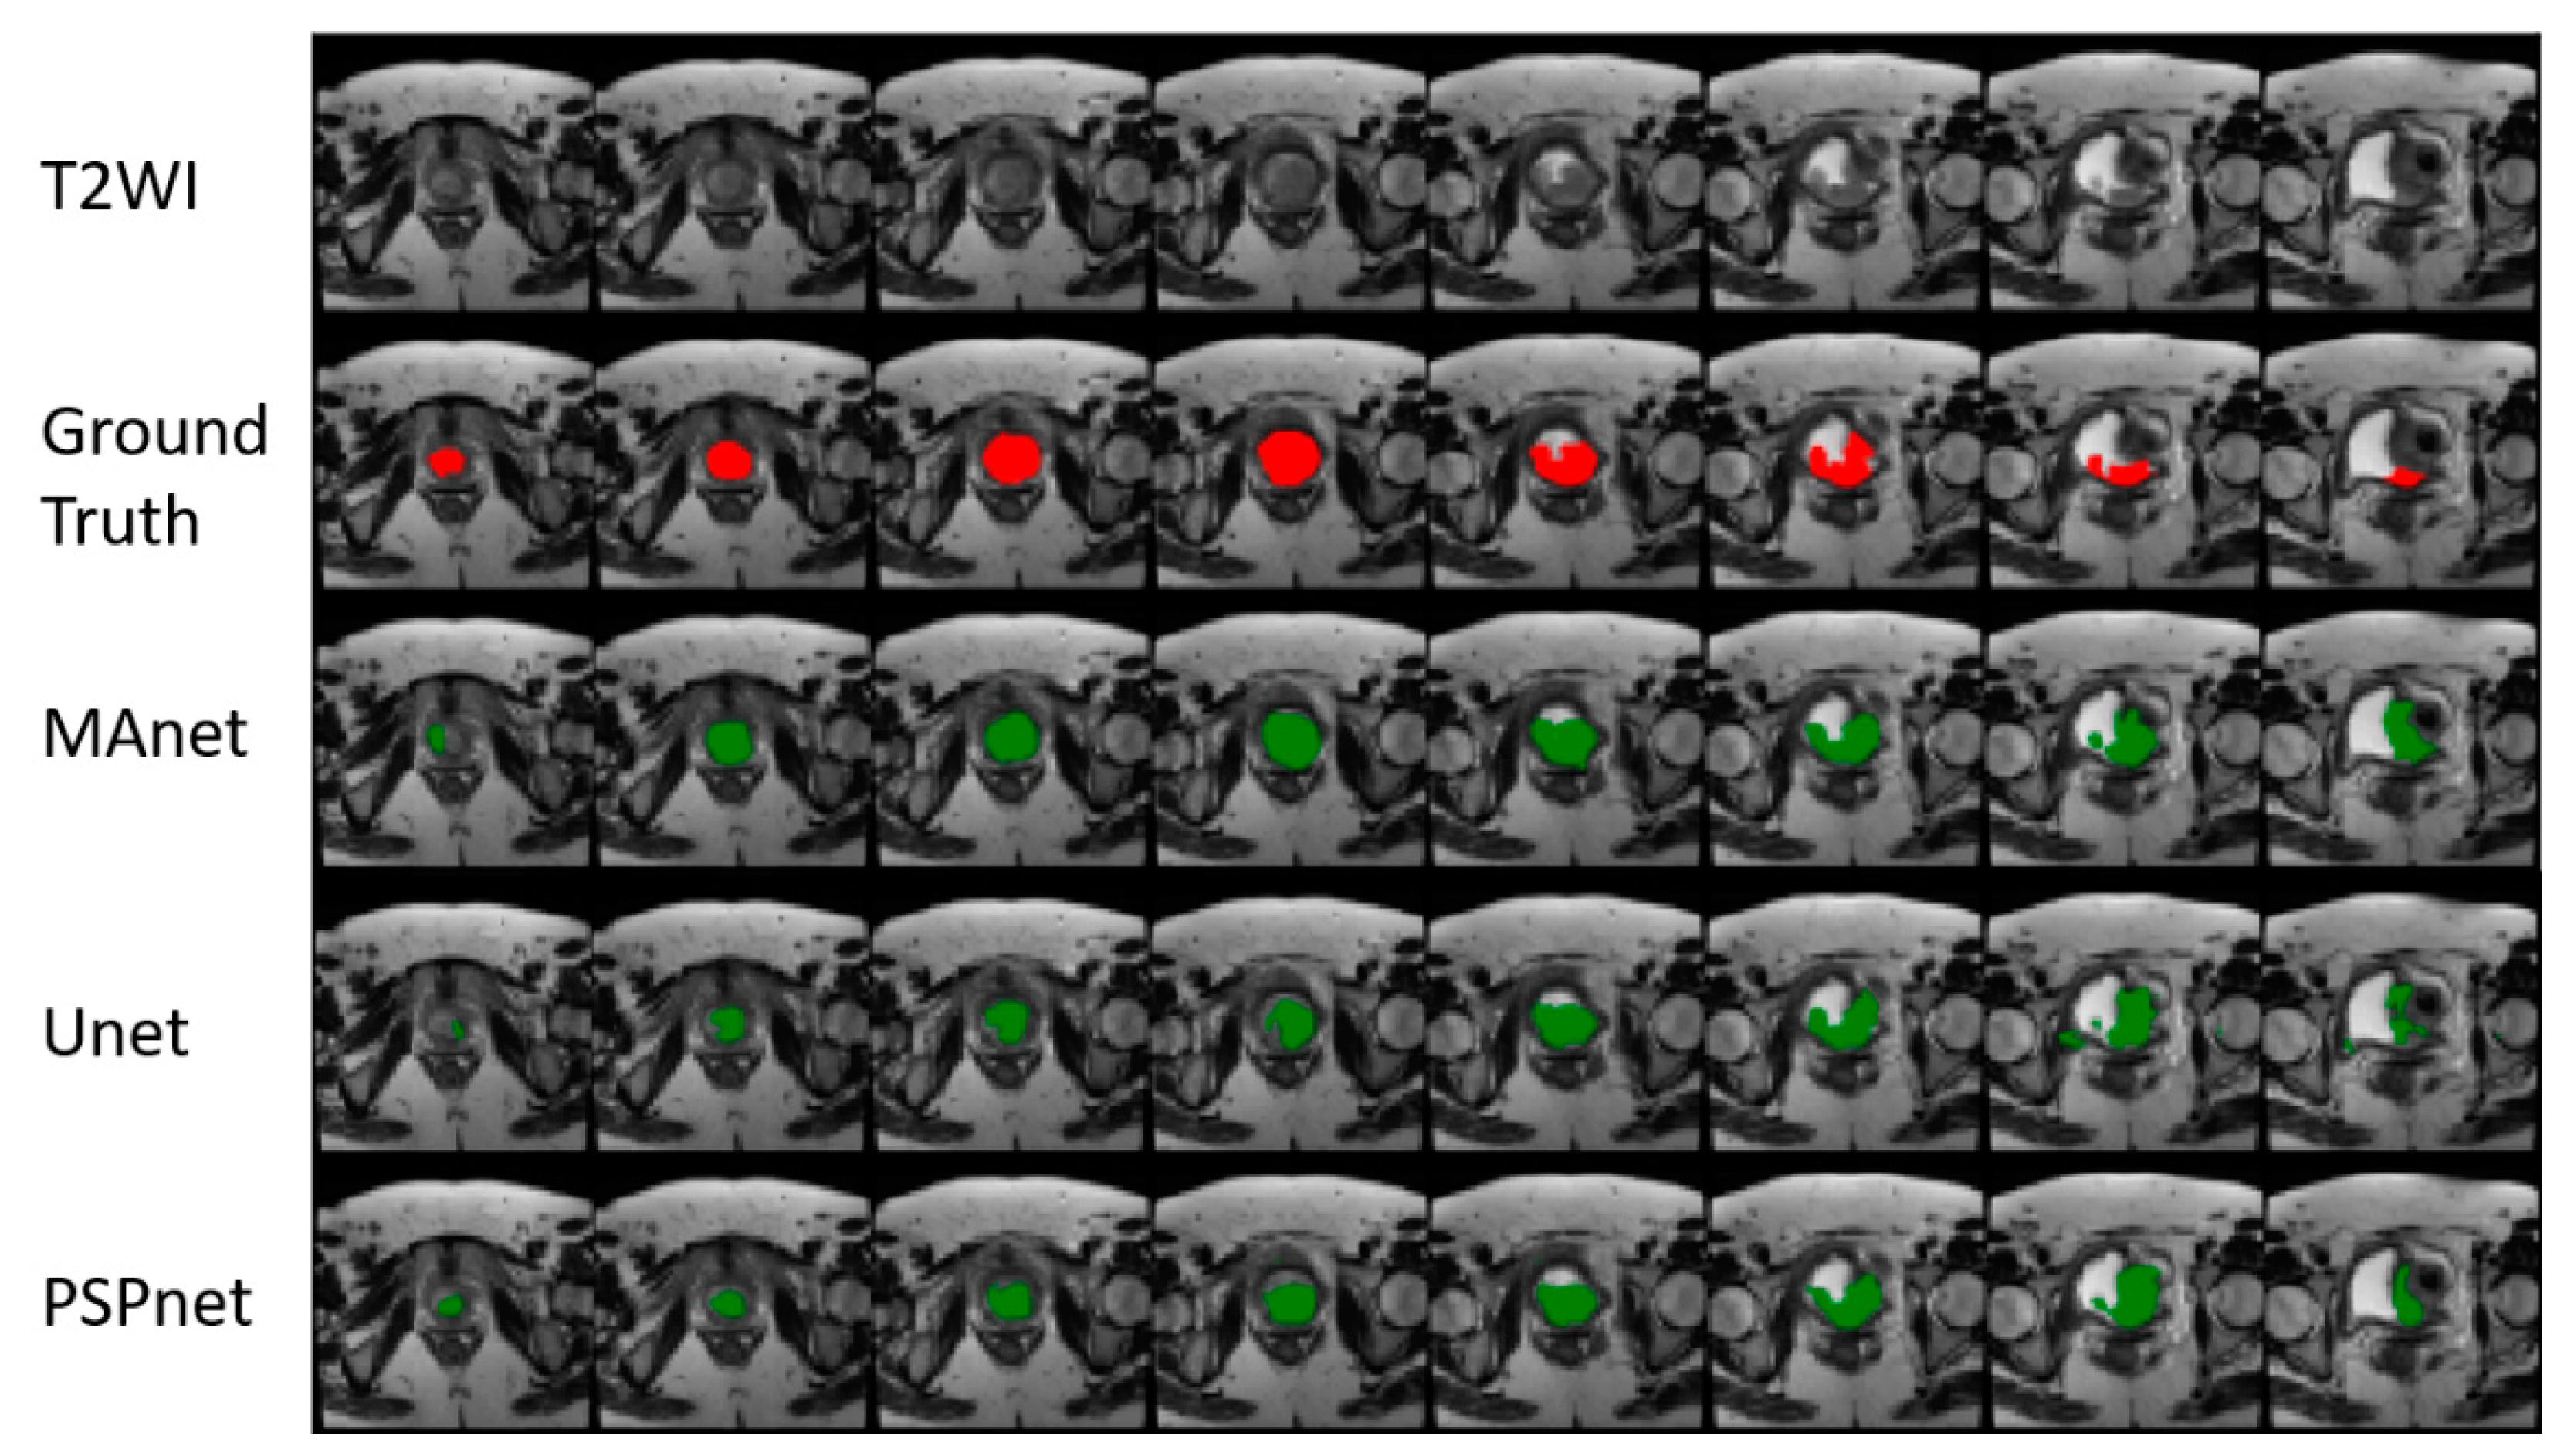

3. Results

| MAnet | LCE | 0.4550 | 0.3175 | 0.2875 | 47.54 | 67.62 | 76.91 | 0.0200 | 0.0200 | 0.0350 |

| LCE + LDSC | 0.5925 | 0.5600 | 0.4650 | 23.92 | 27.52 | 41.23 | 0.0150 | 0.0075 | 0.0100 | |

| LFL | 0.3700 | 0.2575 | 0.2450 | 46.83 | 72.58 | 74.64 | 0.0525 | 0.1025 | 0.1125 | |

| PSPnet | LCE | 0.4200 | 0.4500 | 0.2700 | 52.84 | 56.28 | 78.27 | 0.0175 | 0.0250 | 0.0325 |

| LCE + LDSC | 0.5650 | 0.5075 | 0.4175 | 10.71 | 21.94 | 31.34 | 0.0150 | 0.0175 | 0.0200 | |

| LFL | 0.3825 | 0.3925 | 0.2600 | 47.26 | 45.68 | 80.85 | 0.0125 | 0.0150 | 0.0250 | |

| Unet | LCE | 0.4950 | 0.2900 | 0.2750 | 39.21 | 87.53 | 85.57 | 0.0200 | 0.0200 | 0.0250 |

| LCE + LDSC | 0.5825 | 0.5250 | 0.4525 | 33.86 | 46.09 | 57.34 | 0.0150 | 0.0075 | 0.0150 | |

| LFL | 0.3850 | 0.2725 | 0.2100 | 36.32 | 85.04 | 82.97 | 0.0475 | 0.0925 | 0.1275 |